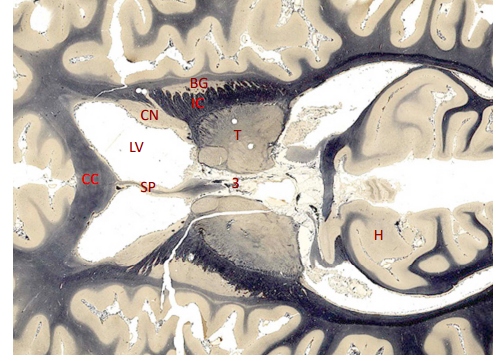

label, note important features